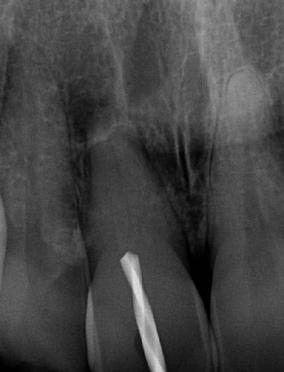

1. a–g. ábrák: A direkt pulpasapkázás lépései. Kiindulási bitewing-felvétel: A meglévő restaurátum közel helyezkedett el a pulpakamrához (a). Kiindulási periapicalis felvétel: Nincs periapicalis elváltozás fennállására utaló jel (b). A pulpaexpozíció (c). A vérzéscsillapítás céljából 20 másodpercen keresztül steril vattagombóccal történő kompressziót követően látható pulpaseb (d). A pulpasapkázás céljából behelyezett anyag, a széli részek tisztázása előtt készült felvétel (e). A röntgenárnyékot nem adó ideiglenes tömés behelyezése után készült felvétel (f). Az első ülés végén a röntgenárnyékot nem adó ideiglenes töméssel ellátott fogról készített röntgenfelvétel (g).

2. ábra: A hat hónapos kontroll alkalmával készített röntgenfelvételen vastag dentinhíd látható a pulpasapkázó anyag alatt.

3. ábra: A hároméves kontroll alkalmával készített röntgenfelvételen megfigyelhető a restaurátum pontos illeszkedése.

A diagnózisunk reverzibilis pulpitis volt. Periapicalis elváltozás jelenlétét nem vélelmeztük. A fogban lévő amalgámtömés eltávolítása során körülbelül egy 3 mm átmérőjű pulpaseb keletkezett a buccalis pulpaszarvnak megfelelően (1. a–g. ábrák) Mivel nem tapasztaltunk jelentős vérzést, és a diagnózisunk reverzibils pulpitis volt, ezért a direkt pulpasapkázás elvégzése mellett döntöttünk.

A kavitást 2,5%-os nátrium-hipoklorit oldattal fertőtlenítettük, majd sűrű konzisztenciájú kalcium-szilikát alapú anyagot (CeraPutty, Meta Biomed) készítettünk elő a direkt pulpasapkázás elvégzéséhez. Az első kezelés végén röntgenárnyékot nem adó ideiglenes töméssel (NexTemp LC, Meta Biomed) zártuk

az üreget annak érdekében, hogy a direkt pulpasapkázásra használt anyag megfelelő pozícióját radiológiailag ellenőrizni tudjuk. A második ülés során kompozit tömőanyagból (Ezfil, Meta Biomed) direkt adhezív restaurátumot készítettünk.

A kezelést követően a beteg tünetmentes volt. A kérdéses fog a kontrollvizsgálatok során végzett szenzibilitástesztekre fiziológiás reakciókat adott. A hat hónapos kontroll alkalmával készített röntgenfelvételen a sérülésnek megfelelően széles dentinhidat észleltünk (2. ábra). A restaurátum a hároméves kontroll során is megfelelőnek bizonyult (3. ábra)